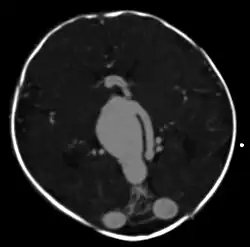

Cerebral arteriovenous malformation

| Large arteriovenous malformation of the parietal lobe | |

A cerebral arteriovenous malformation (cerebral AVM, CAVM, cAVM, brain AVM, or BAVM) is an abnormal connection between the arteries and veins in the brain—specifically, an arteriovenous malformation in the cerebrum.[1]

vein of Galen malformation